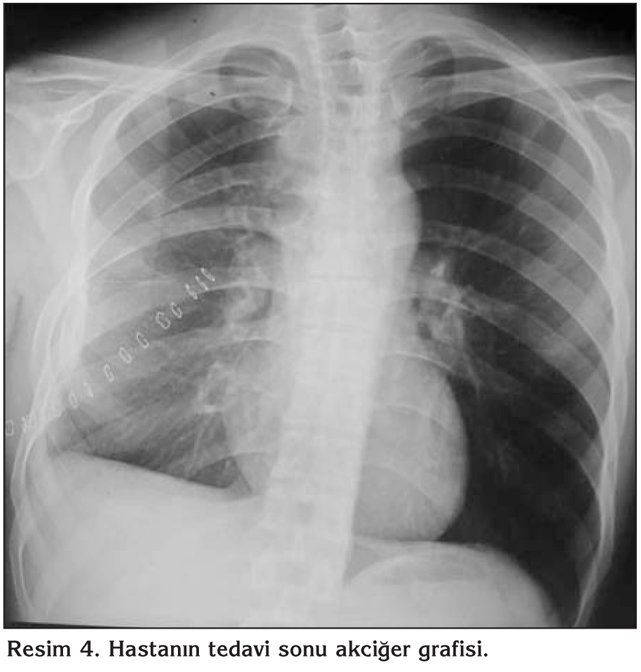

Yirmi bir ya??ndaki erkek hastaya, 2011 y?l? ?ubat ay?nda sol testiste a?r? ve ciltte ak?nt? ?ikayetiyle ba?vurdu?u merkezde, testiste kitle saptanarak, malignite ??phesiyle or?iektomi yap?lm??t?r. Hastan?n or?iektomi patolojisi kazeifiye gran?lomat?z iltihap olarak raporlanm?? olup, adli olgu/h?k?ml? olan hastan?n, kendisinden ve sevk i?lemlerinden kaynaklanan nedenlerle tedavisi ba?lanamam??. 2011 y?l? Eyl?l ay?nda g???s ve s?rt a?r?s? ve bu s?re zarf?nda yakla??k 10 kg kilo kayb?yla merkezimize ba?vuran olgunun g???s ?n y?z?nde fluktuasyon veren apse formasyonu d???nda fizik muayene bulgular?nda patoloji saptanmam??t?r (Resim 1). Laboratuvar incelemede; tam kan say?m? ve biyokimyasal de?erleri normal s?n?rlarda idi. Posteroanterior akci?er grafisinde paratrakeal dansite art???, yan grafide sternum ?n?nde yumu?ak doku art??? ile bombele?me mevcuttu (Resim 2). Toraks ve bat?n bilgisayarl? tomografi (BT) incelemesinde; toraks ?n duvar? sternum anteriorunda ve sol lateralinde, cilt alt? dokularda hipodens yer kaplay?c? lezyon, posterior mediastende paravertebral alanda en geni? yerinde 42 mm kal?nl??a ula?an vertebra korpusunda ve sa? kotlarda destr?ksiyona yol a?an heterojen dansitede yer kaplay?c? lezyon, sa? hemitoraks posteriorunda D10 vertebra korpusu solunda ve kotlarda destr?ksiyona yol a?an 40 x 25 mm boyutunda yumu?ak doku lezyonu, sa? hemitoraksta pl?rezi izlendi (Resim 3). G???s ?n y?z?nde fluktuasyon veren apseye yap?lan i?ne aspirasyonuyla p? aspire edildi ve Erlich Ziehl Neelsen aside diren?li boyama y?ntemiyle incelemede aside diren?li basil (ARB) g?r?lmedi. Apse materyalinin aerop ve anaerop k?lt?rlerinde ?reme olmad?. Al?nan balgam ?rne?inde direkt muayenede ARB negatif kald?. Yap?lan tetkikler sonucunda testis t?berk?lozunun yan? s?ra pl?rezi, g???s ?n duvar?nda so?uk apse, vertebra ?n y?z?nde paravertebral apse (Psoas apsesi), vertebralarda destr?ksiyon saptand?. Olguya testis t?berk?lozunun yan? s?ra yayg?n tutulum nedeniyle rifampin, izoniazid, pirazinamid ve etambutol olmak ?zere antit?berk?loz tedavi ba?land?. Merkezimize m?racaat?nda pl?rezide d?zelme mevcuttu (Resim 3B). Tedavi alt?nda, vertebra destr?ksiyonu a??s?ndan n?ro?ir?rji kons?ltasyonlar? devam eden hastan?n, tedaviye ra?men g???s ?n y?z?ndeki apsede d?zelme olmamas? ve hastan?n a?r? ve gerginlik ?ikayetleri olmas? nedeniyle g???s t?p? tak?ld? ve apse bo?alt?larak hasta rahatlat?ld? (Resim 3B). Takiplerde hastadan al?nan balgam ?rne?inin spesifik k?lt?r? negatif kald?. G???s ?n duvar?ndan aspire edilen p?den yap?lan spesifik k?lt?rde Mycobacterium tuberculosis ?redi. ?la? duyarl?l?k testlerinde diren? paterni saptanmad?. Vertebralara y?nelik ?ekilen manyetik rezonans g?r?nt?leme (MRG)'de; C5-6 diskinde posterior sa? paramedian prot?zyon, T1-T8 vertebralarda korpuslarda destr?ksiyon ve intervertebral foramen yoluyla spinal kanal i?ine uzanan 18 x 6.5 x 8.5 cm boyutlar?nda ankaps?le y?ksek dansiteli koleksiyon mevcuttu. Beyin ve sinir cerrahisi ile kons?lte edilen hastaya 2011 y?l? Aral?k ay?nda T3-T4 torakotomi + apse drenaj operasyonu yap?ld?. Postoperatif d?nemde ?ekilen MRG ile apsenin bo?alt?ld??? verifiye edildi. Tedavi sonras? lezyonlar geriledi ve yeni lezyon olu?mad? (Resim 4). Hasta halen ?ikayetsiz olup, t?berk?loz tedavisi sonland?r?lm??t?r. Hastal?k seyrine bak?ld???nda; adli olgu/h?k?ml? hastada, hastan?n kendisinden (hasta gecikmesi), sevk i?lemlerinden (sevk zincirinde gecikme) ve doktor gecikmelerinden (doktor gecikmesi) kaynaklanan yedi ayl?k bir tedavi gecikmesi olmu? ve ba?lang??taki testis t?berk?lozu, yayg?n t?berk?loz ile sonlanm??t?r.

Resim 4